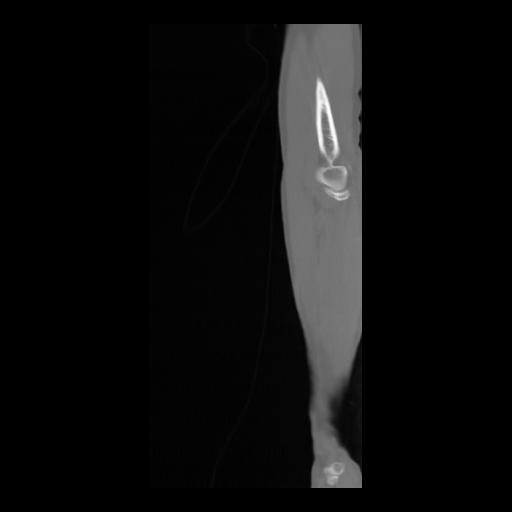

36 CUERPO,CE,Sagittal,3.000,CUERPO,Sagittal,